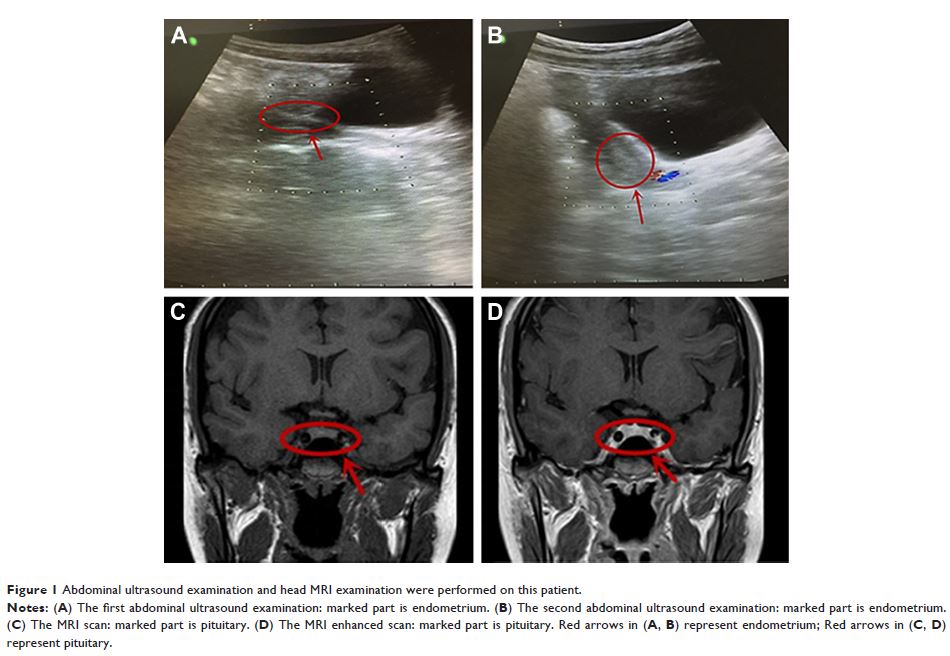

阿立哌唑组合用于逆转由帕潘立酮诱导的催乳素水平的升高